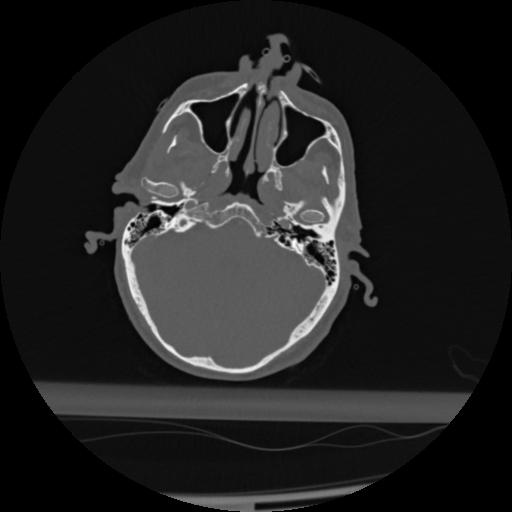

22 ANGIO,CE,Vol,0.5,ANGIO,,